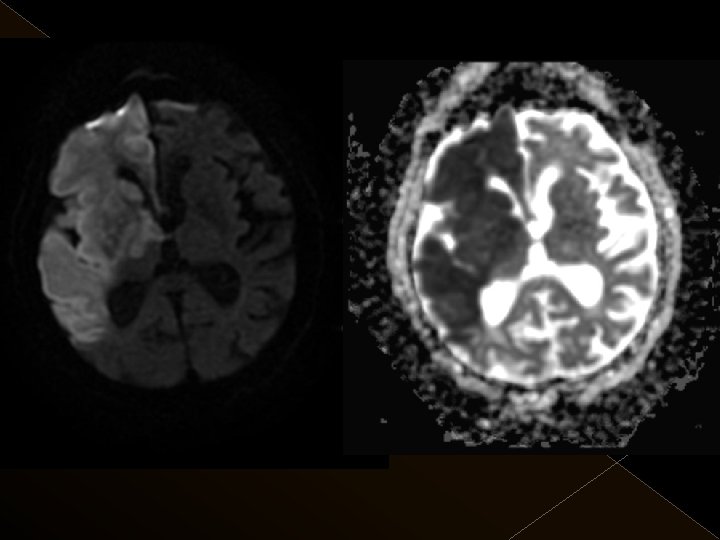

Görüntüleme İşlem öncesi § Bazal kontrastsız BT § BT anjiografi (varsa perfüzyon BT ) § MR (DW, ADC) İşlem sonrası § MR ( DW, ADC, SWI) § 24. saatte kontrol BT veya MR